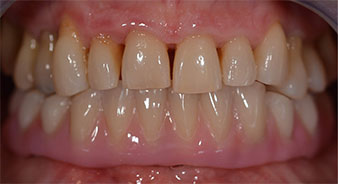

The 64-year-old patient presented with residual dentition of teeth 38, 33 and 43 and a clasp denture in the mandible (Fig. 1 and 2).

The impression and bite registration were then performed so that the dental technician could begin producing the provisional restoration immediately. This was then screwed in on the same day (Fig. 17 and 18).

Following the time required for the osseointegration, the final impression of the implants could be performed and the final denture produced accordingly (Fig. 19 and 20). At this point, the dentist and patient were able to decide together whether to use a ceramic or acrylic veneer and a zirconium or metal framework. In this case, Dr. Pascu’s team decided on an acrylic veneer based on the unclear prognosis for the maxillary dentition and the fact that tooth 24 is elongated. This type of veneer is generally considerably easier to adapt and can thus be subsequently altered to reflect the new situation in the maxilla.